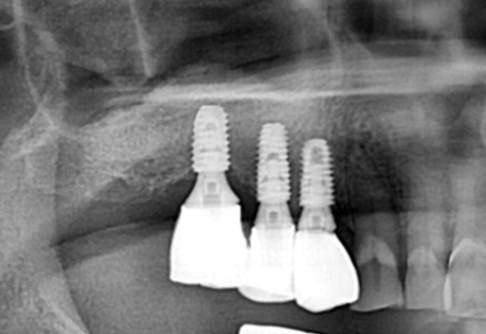

Before

After

위 치료 사례는 굿프렌즈치과에서 직접 치료를 받은 환자 분의 사례로 직접 동의를 얻어 게재되었습니다.

치료사례 더보기 +